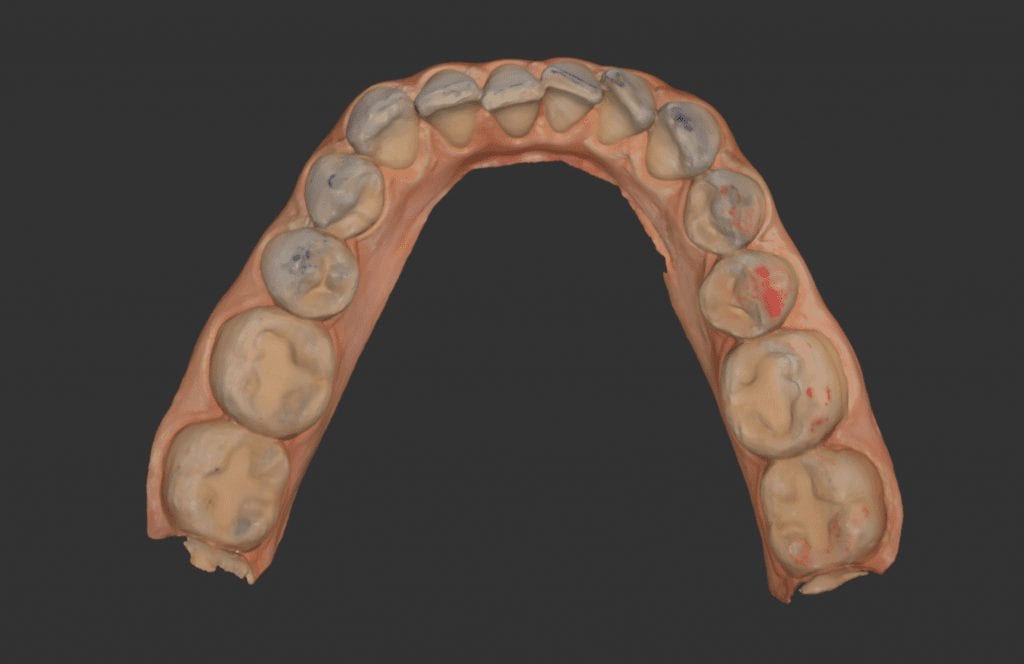

In this particular clinical case, the patient has opted to utilize clear aligners to straighten some anterior crowding. The Medit i500 was used to capture both the upper and lower jaws, and articulating paper was used to marked the clinical contact points.

In this video, you can see how we verify the accuracy of the occlusal contacts. In the software, you can open the articulated arches and look for contact points made digitally and you can compare those to the clinical marks left with articulating paper.